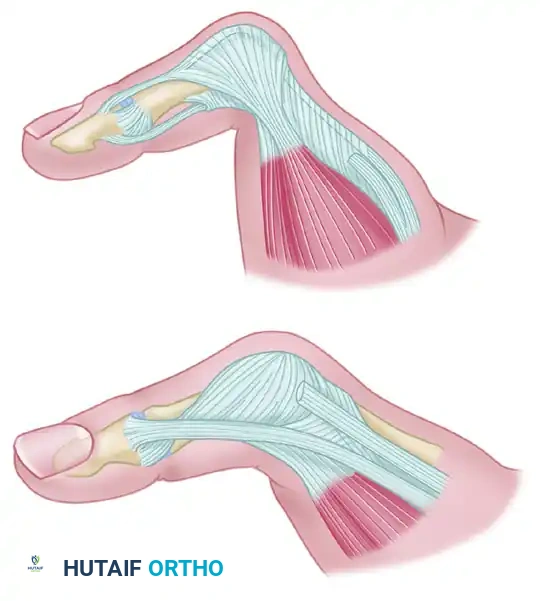

2. Extensor Apparatus and Capsular Exposure

Once the superficial nerves are protected, the extensor apparatus is addressed to gain access to the joint capsule.

- Identify the extensor pollicis brevis (EPB) tendon and the radial aponeurotic fibers.

- Make a longitudinal incision through the EPB tendon and the radial sagittal band fibers. This interval allows for excellent exposure of the underlying dorsal capsule without compromising the centralizing forces of the extensor pollicis longus (EPL).

FIGURE 73-40B: Incision through the extensor pollicis brevis tendon and radial aponeurotic fibers exposing the dorsal capsule.